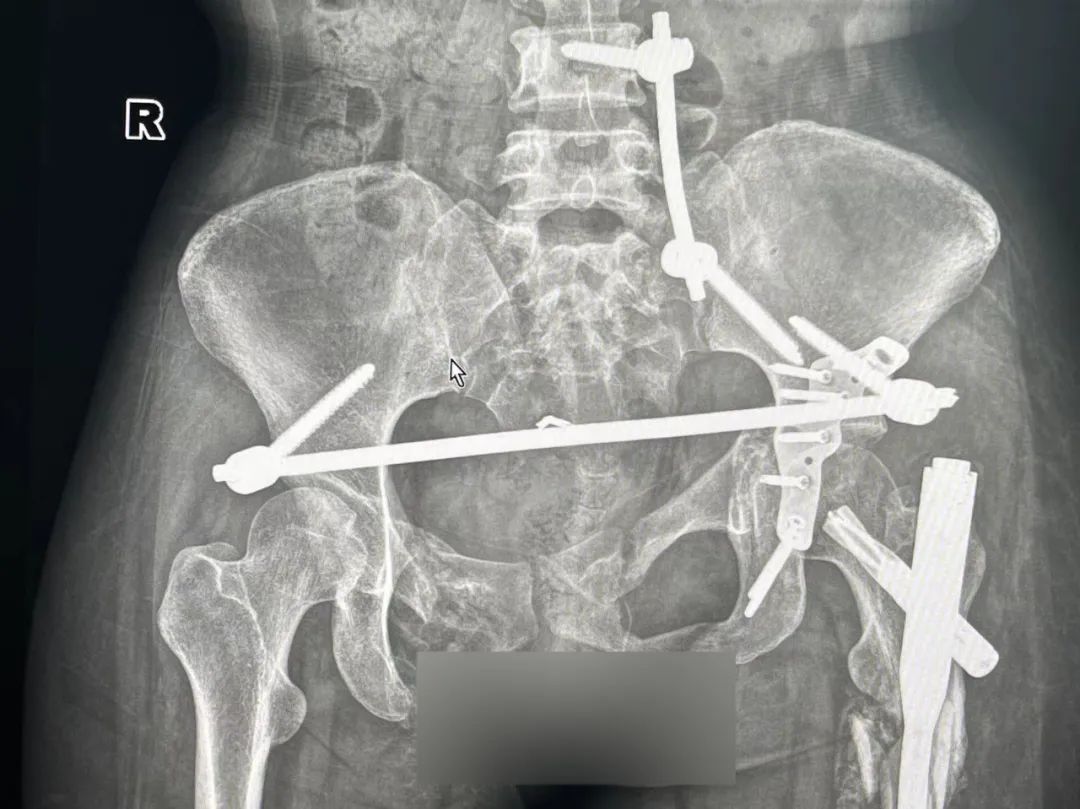

考虑到小高才 20 岁,不做手术的话将终身卧床,萨米医疗骨科团队立即组织了全科室讨论,并为小高制定了详尽的手术方案——骨盆骨折切开复位内固定术,手术由丁斌主任主刀。

「因此骨盆骨折手术难度大、手术风险高,骨盆骨折内固定术一直是骨科领域最复杂、最具挑战性的手术之一。但我们有丰富的经验和充足的准备,有信心可以做好它。」萨米医疗骨科丁斌主任如此说道。

最后在丁斌主任及骨科团队的齐心协力下,小高的复杂陈旧性骨盆骨折手术顺利完成!